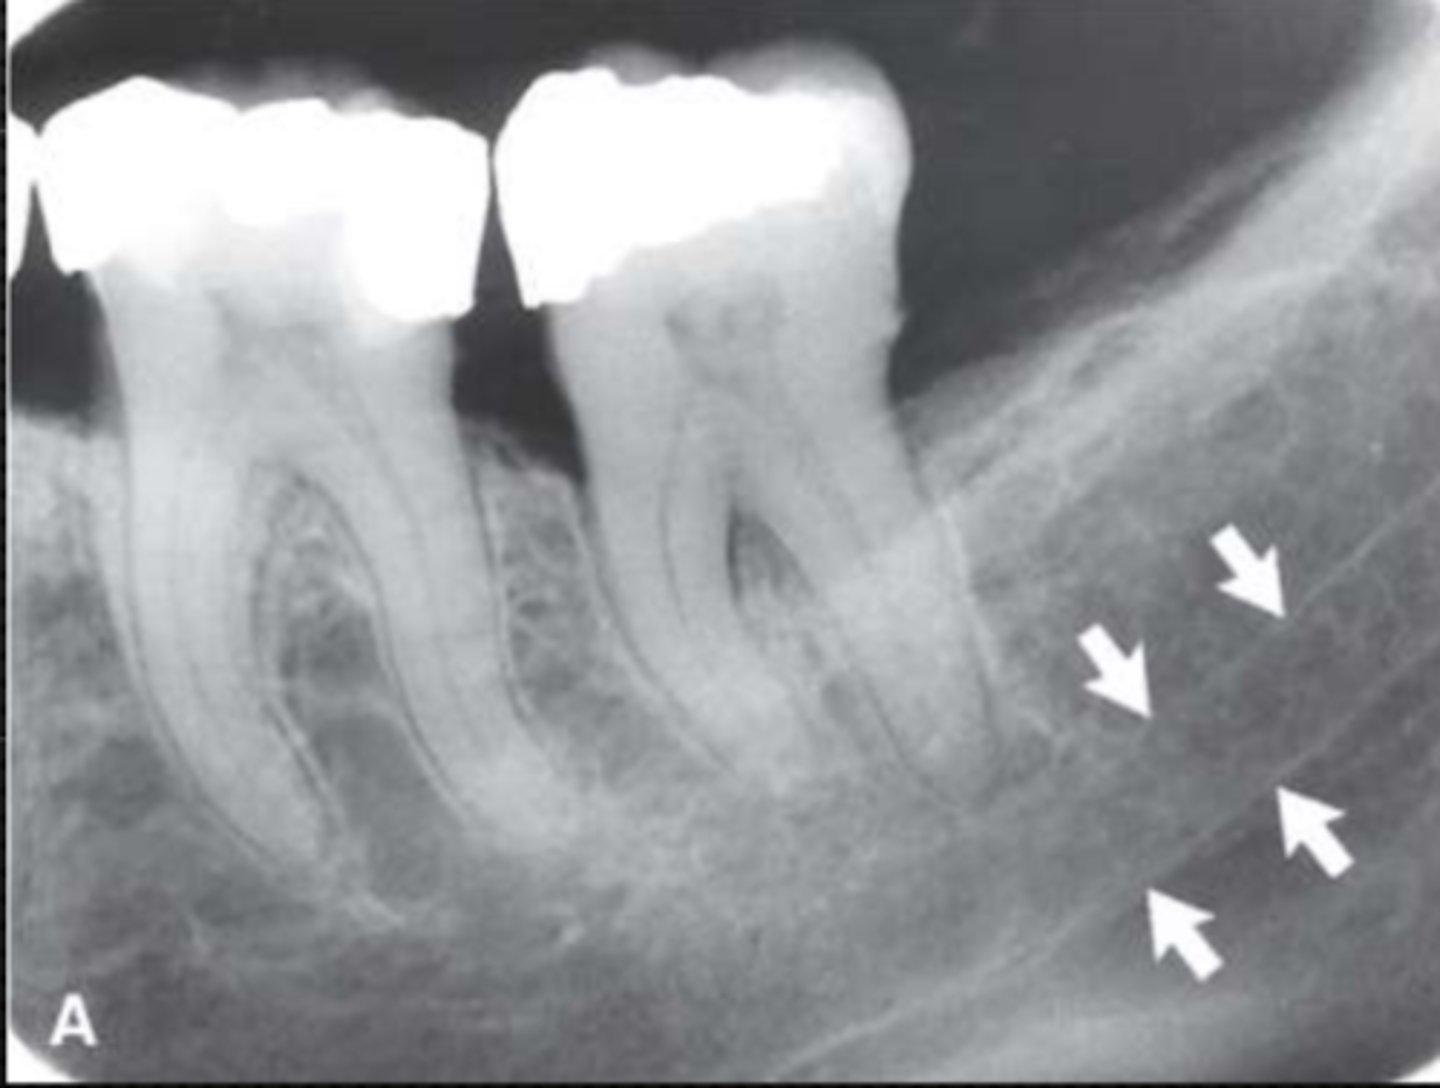

Mandibular canal

Identify the structure

<p>Identify the structure</p>

29

New cards

Identify the radiolucent structure

<p>Identify the radiolucent structure</p>

30

Nutrient canals (neurovascular canals)

31